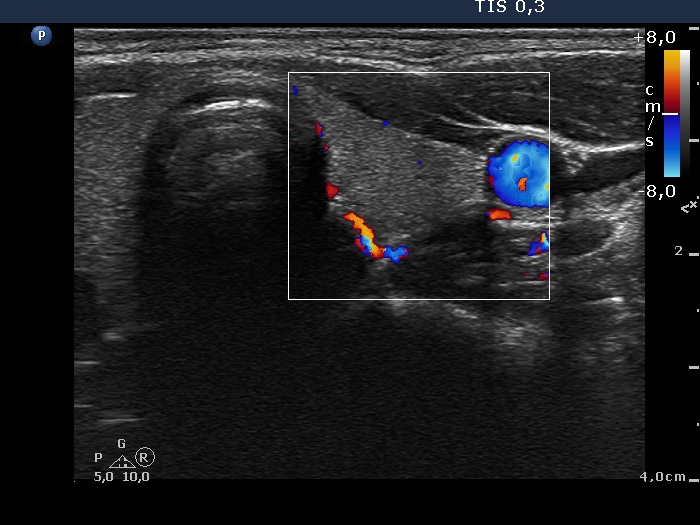

Right lobe, color Doppler mode

Left lobe, color Doppler mode

- There are two situations in Graves 'disease where circulation is increased. At the stage of disease activity and when hypothyroidism is observed with medication. In the former case, the blood flow is almost always increased, in the latter it can be decreased and increased.